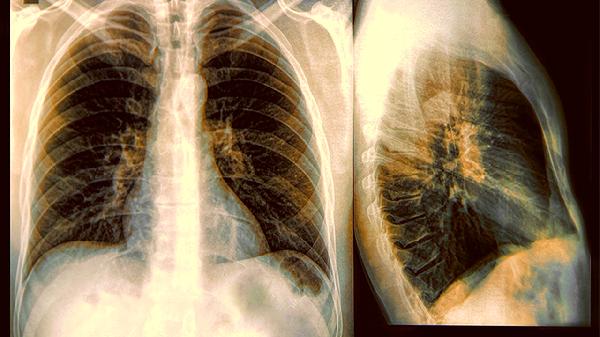

一男子肺癌晚期,从不抽烟喝酒,医生问后才知晚上常做这几件事

谁能想到,一个不碰烟酒、作息规律的中年人,体检报告上会赫然出现"肺癌晚期"四个字?当医生追问生活习惯时,真相才浮出水面——那些被我们忽视的夜间行为,正在悄悄摧毁呼吸系统。